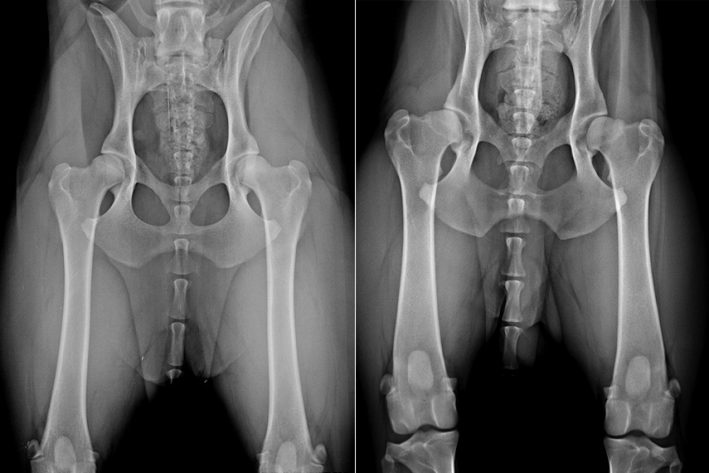

Normale Hüfte (links) versus Hüftgelenksdysplasie (rechts)